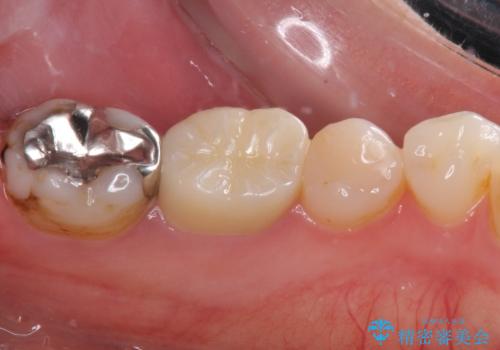

- 奥歯の詰め物や周辺の歯が欠けてしまったとのことで来院された患者様です。

上顎は、元々の詰め物が小さく、欠けた範囲も大きくなかったため、セラミックインレーにて修復治療を行うこととしました。

一方下顎は、元々のむし歯の範囲が広かったため、長期的な予後を踏まえ、セラミッククラウンにて補綴治療を行うこととしました。